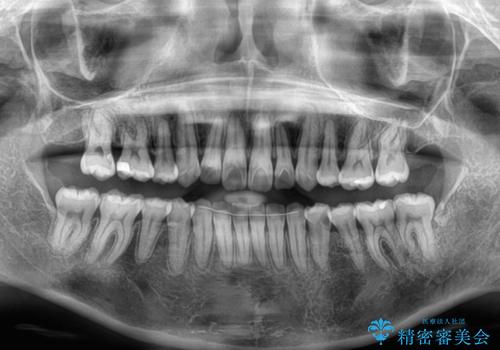

- 前歯のデコボコを治したいとのことで来院された患者様です。

上下顎ともに歯列全体の後方移動とIPR(歯と歯の間を削る)によってデコボコが解消するように設計し、インビザラインにより治療を行うこととしました。

下顎前歯は後戻りを起こしやすいため、舌側を細いワイヤーで固定し、マウスピース型リテーナーで保定を行うこととしました。